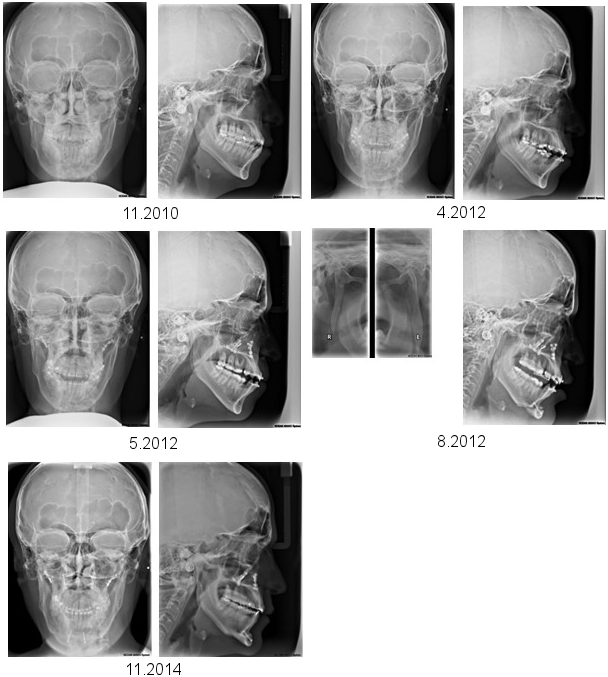

Figure 4: A series of cephalometric radiographs depicting the patient in anterior-posterior (left) or lateral projection (except the fourth series of radiographs).

The first series shows the dental and skeletal relations prior to treatment.

The second series shows the final position after completion of orthodontics prior to the first surgical procedure.

The third series shows the position of the bones following maxillary osteotomy.

The fourth series shows the vertical osteotomy of each mandibular ramus (left side), and the position of the jaws, including chin osteotomy, after the second surgical procedure.

Finally, the fifth series demonstrates the relation of the jaws after completion of post-surgical orthodontics.